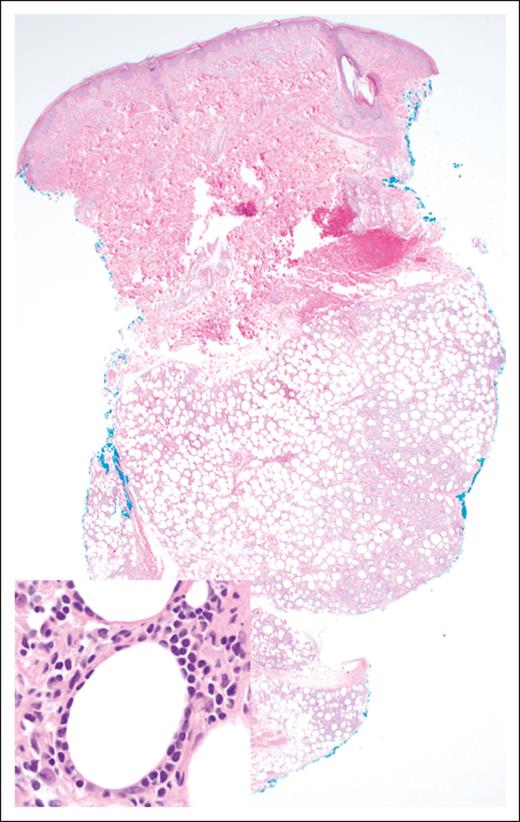

The histopathologic features of EATLs are highly variable. The neoplastic lymphocytes are generally medium to large in size and show varying degrees of pleomorphism, with some cases displaying immunoblastic or anaplastic cytomorphology.17 The tumors are frequently accompanied by a mixed inflammatory infiltrate composed of histiocytes, eosinophils, and plasma cells, which may obscure the malignant cells (Figure 1). Portions of small intestine away from the tumor mass frequently show typical histopathologic features of celiac disease.18 EATLs typically express cytoplasmic CD3, CD2, CD7, CD103, and cytotoxic markers (TIA-1, perforin, and granzyme-B) and lack CD4, CD5, and CD56 expression. Most cases do not express surface CD3 and TCR. Approximately one-third of patients are CD8+18-20 and intracellular TCRβ expression is detected in one-quarter of patients.21 CD30 expression is common in patients exhibiting anaplastic morphology, but ALK-1 is always negative,17 and the neoplastic T cells are negative for Epstein-Barr virus (EBV).

EATL. (A) Clusters of pleomorphic lymphoma cells reside within a mixed inflammatory background, focally infiltrating the small intestinal epithelium (original magnification, ×500; hematoxylin and eosin [H&E] stain). (B) The large intestine contains a sheet-like proliferation within the lamina propria (original magnification, ×400; H&E stain).